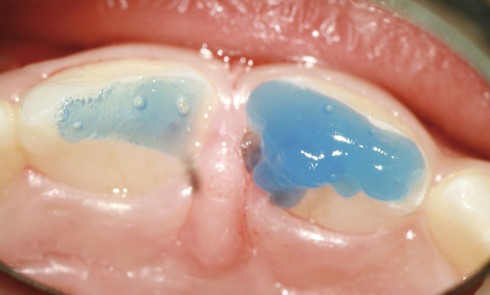

Article réservé à nos abonnés Les secrets de l’isolation

Les feuilles de digue Elles peuvent être avec ou sans latex. Actuellement, les feuilles à base de latex, de préférence...